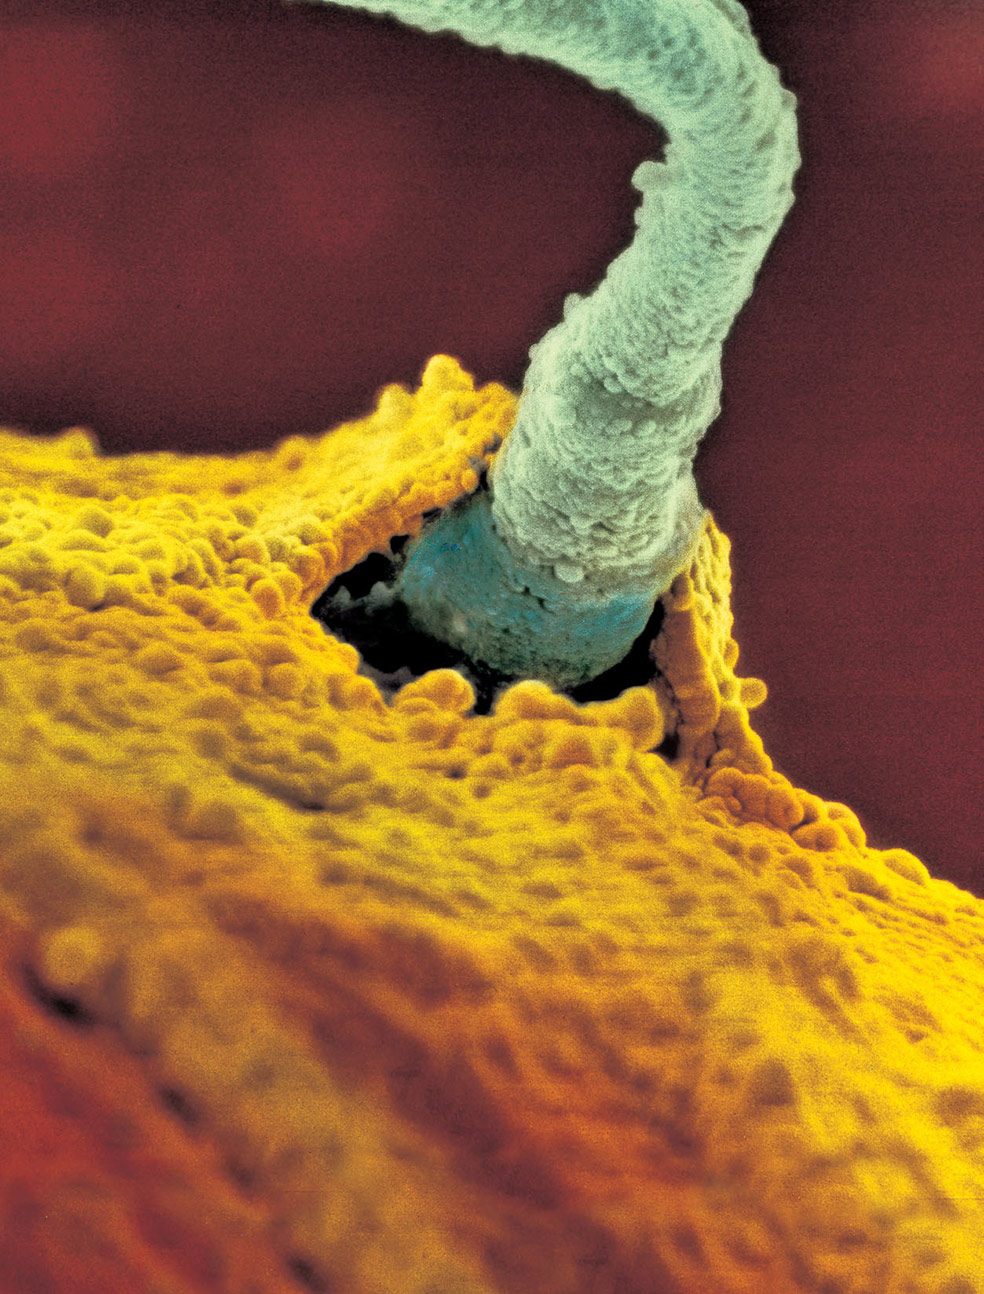

El encuentro decisivo...

Han pasado entre tres y siete horas desde la relación sexual. Un espermatozoide, entre 300 millones, logra su objetivo: penetrar en el óvulo. Inmediatamente, la superficie de éste cambia para que no entre ninguno más.